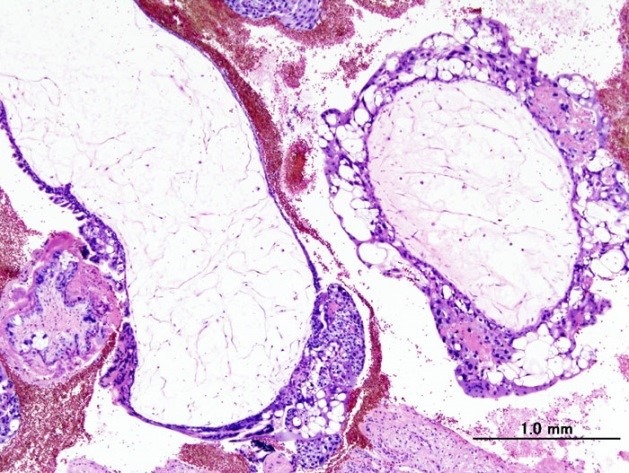

- частичный пузырный занос. Образуется при оплодотворении яйцеклетки сразу двумя сперматозоидами. Такой эмбрион содержит дополнительный набор хромосом, и, к сожалению, является нежизнеспособным;

- полный пузырный занос. Образуется при оплодотворении яйцеклетки с отсутствием хромосом. При дальнейшем делении клеток отцовские хромосомы удваиваются и становятся заменой материнских, однако эмбрион не образуется.

Полный пузырный занос

Эти доброкачественные опухоли диагностируются у 70 % больных, при этом как при полном, так и неполном пузырном заносе наблюдается только разрастание трофобластической ткани и превращение ворсинок хориона в пузырьки. Однако в 20 % случаев трофобласты приобретают способность к малигнизации и метастазированию. По мере распространения злокачественных клеток в окружающие ткани различают инвазивный пузырный занос, диссеминированный пузырный занос, хорионкарционому, трофобластическую опухоль плацентарного ложа и эпителиоидную трофобластическую опухоль.